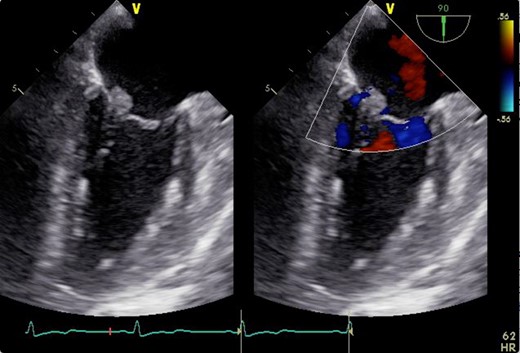

A 46-year-old woman with a history of long-standing SLE and APLS for >17 years and two recent cerebral infarctions was referred to our emergency department with a sudden-onset chest pain and dyspnea (New York Heart Association functional class III). Her usual steroid dose was 10 mg per day. Secondary to SLE associated thrombocytopenia she was anticoagulated with dabigatran. The EKG was consisted with anterior wall STEMI. Troponin level was 1.850. Coronary angiography showed obstruction at the distal left anterior descending and left circumflex arteries (Fig. 1). Transesophageal echocardiography demonstrated a preserved ejection fraction of the left ventricle and a mobile vegetation measuring 9 × 6 mm2 at the mitral valve (Fig. 2). Blood cultures were all negative. She urgently underwent mitral valve replacement through mini right thoracotomy to prevent further thromboembolic events. Cardiopulmonary bypass was undertaken femoral arterial and femoral and internal jugular venous cannulation. We did not perform coronary artery bypass graft because the obstructed arteries were quite distal. We identified a mass at the mitral A2 segment rough zone and two very small lesions at the A3 segment without annular calcification or submitral apparatus disease (Fig. 3). A2 segment was largely affected and shortened; therefore, we decided to not proceed the valve repair. Replacement was performed with a 27/29 mm On-X mechanical prosthesis (Medical Carbon Research Institute, LLC, Austin, TX, USA). Anterior and posterior chordae were spared. Aortic cross clamp time was 242 min and cardiopulmonary bypass time was 289 min. A pathological examination of excised valve leaflets demonstrated a fibrin thrombus without an evidence of microorganisms. The postoperative course was uneventful, and she was discharged 14 days after the surgery. She was followed up for 6 months, and her condition was stable.

2D transesophageal echocardiogram showing a thickened mitral valve with vegetation that can be seen on the anterior mitral valve leaflet. Image on the right is a color flow Doppler view showing no mitral regurgitation and stenosis.